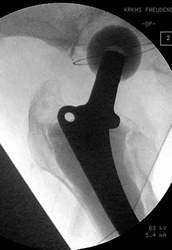

Versorgung einer Femurfraktur bei liegender Totalendoprothese

Diese Fraktur ereignete sich 8 Wochen nach Prothesenwechsel. Der Wechsel war bereits problematisch, Frakturen wurden mit Drahtcerclagen befestigt. Es handelte sich jetzt um eine Stückfraktur.